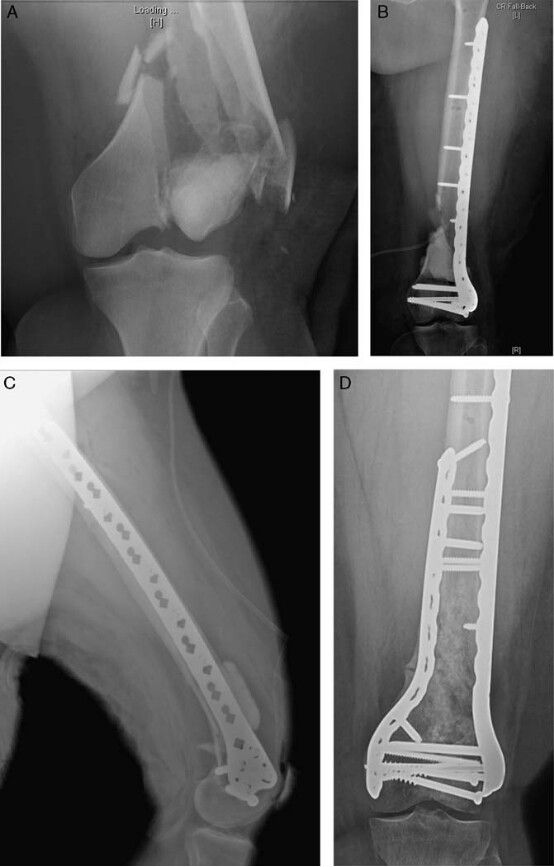

有些時(shí)候,由于嚴(yán)重的骨質(zhì)缺損,任何一種內(nèi)固定方法都很難固定骨質(zhì)疏松性股骨遠(yuǎn)端骨折。對(duì)于這些患者,考慮到最終的功能結(jié)果會(huì)很差,有的學(xué)者建議直接采用膝上截肢的方法進(jìn)行治療。但是,基于全關(guān)節(jié)置換技術(shù)的發(fā)展以及肩部、肘部、髖部骨折全關(guān)節(jié)置換所取得的良好療效,在骨質(zhì)疏松性股骨遠(yuǎn)端骨折中也開(kāi)始使用全關(guān)節(jié)置換方式進(jìn)行治療(圖 3)。

圖 3 為 82 歲男性平地摔倒。 A 為前后位 X 線顯示骨骼骨質(zhì)較差,長(zhǎng)的鋼板和螺釘下面存在嚴(yán)重的粉碎。B 為關(guān)節(jié)部位的軸向 CT 顯示關(guān)節(jié)面無(wú)法重建; C 和 D 為股骨遠(yuǎn)端假體置換的術(shù)后影像。該治療方法通常被保留用于嚴(yán)重骨質(zhì)不良、骨量缺損和關(guān)節(jié)面無(wú)法重建的老年患者

事實(shí)上,一項(xiàng)研究表明,在 13 例采用全膝關(guān)節(jié)置換治療的股骨遠(yuǎn)端骨折患者中,有 11 例患者恢復(fù)到了受傷前的功能水平。全關(guān)節(jié)置換的主要優(yōu)勢(shì)在于術(shù)后可以即刻負(fù)重,有助于降低肺炎和血栓的發(fā)生率。

關(guān)節(jié)置換手術(shù)可以被用于骨量較差、既往存在骨關(guān)節(jié)炎、關(guān)節(jié)攣縮、骨折不愈合、內(nèi)固定物失敗的患者。骨質(zhì)疏松性股骨遠(yuǎn)端骨折的全關(guān)節(jié)置換適用于低需求的、存在嚴(yán)重骨質(zhì)缺損的老年患者,手術(shù)治療的目的是為了止痛和部分恢復(fù)受傷前的功能。由于骨折類(lèi)型和骨量缺損的不同,標(biāo)準(zhǔn)的全膝關(guān)節(jié)置換通常不太適合股骨遠(yuǎn)端骨折,從而需要使用翻修型膝關(guān)節(jié)假體或者是翻修型股骨遠(yuǎn)端假體。